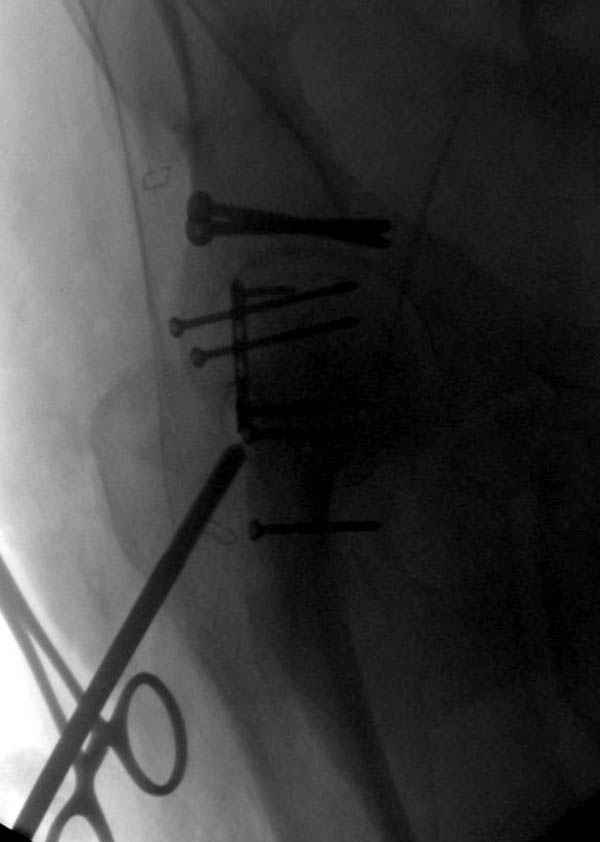

Не хотелось отклонятся от основной темы, поэтому здесь краткие ответы..

Латеральное положение облегчает проведение тракции через вертел, за 5 мм стержень за вертел (грузом через тракционное приспособление), на обычном рентгенопрозрачном операционном столе, а для положения на животе, наверное, Judet Table более приемлем, потому что там имеется латеральное тракционное устроиство.

Там множество обычных 2.7 мм шурупов, потом идет фиксация основными пластинами.

Снимки здесь....